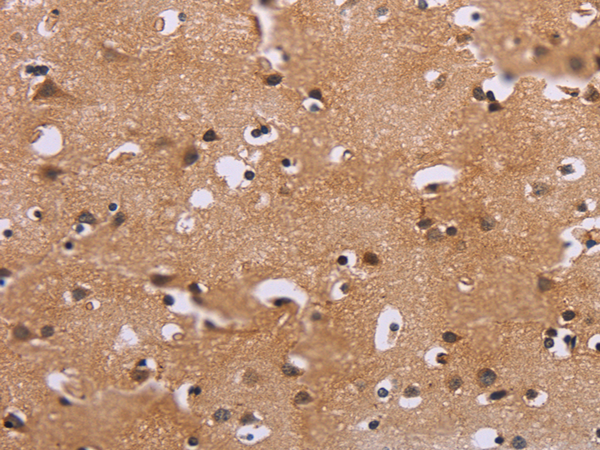

IHC positive control: |

Human thyroid cancer and Human brain |

IHC Recommend dilution: |

50-200 |